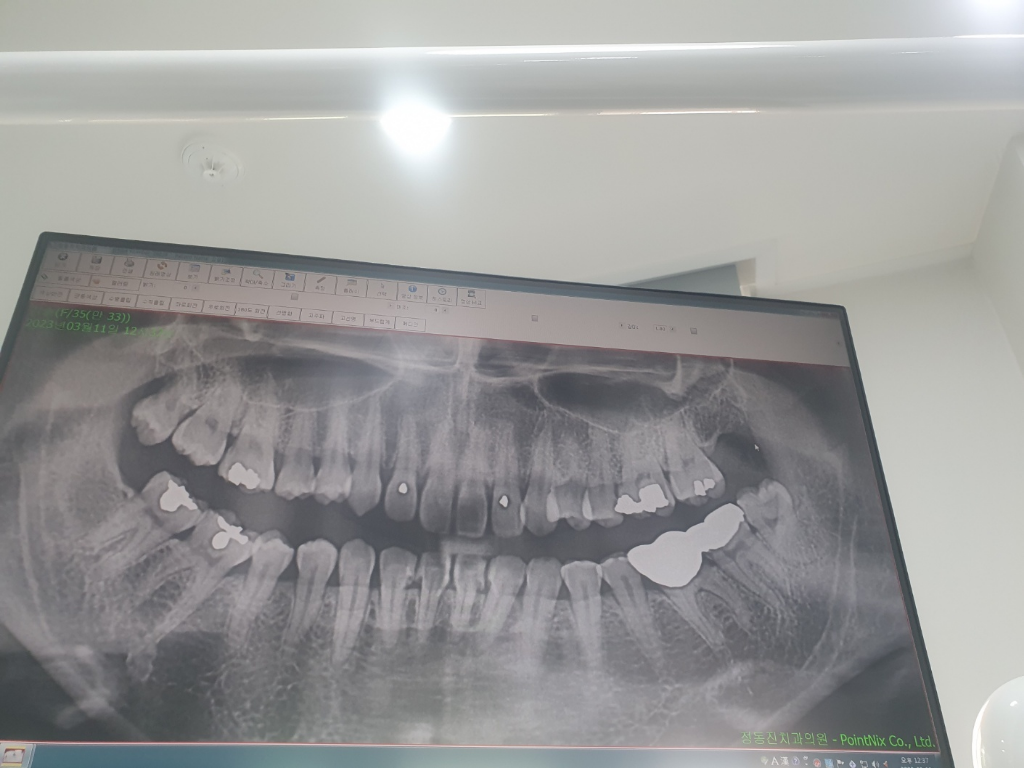

저정도는 잇몸뼈가 내려갓거나 잇몸이 내려간건 아닌거 같습니다. 저정도 공간은 대부분 잇습니다.

파노라마 상에서는 잇몸 뼈가 나빠보이지 않습니다.

사진상으로 잇몸뼈는 괜찮아 보입니다. 잇몸에염증이 생겼다가 낫는 과정에서. 퇴축되기도 합니다.

잇몸뼈가 심하게 녹은 상태는 아닙니다 블랙트라이앵글은 치간유두라고 하는 치아와 치아 사이 잇몸 부위가 다 채워지지 않아 생기는 것입니다 뼈보다는 잇몸 연조직 문제입니다